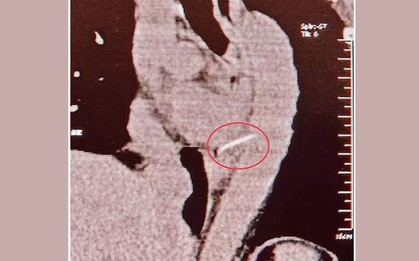

Sau khi biết nguyên nhân dẫn đến các cơn đau thắt ngực của mình không phải là do bệnh hen hay tâm trạng lo lắng mà do nguyên nhân kinh khủng hơn, cô sinh viên này không biết nên khóc hay cười.